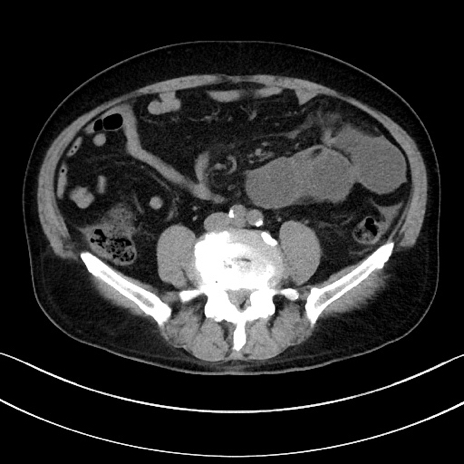

冠状断像

【症例】70歳代男性

【主訴】腹痛

【現病歴】今朝から腹痛あり。全体的に痛い。特に左上の方。排ガスが今日はない。冷や汗が出る。

【既往歴】直腸癌術後

【身体所見】左側腹部〜上腹部に圧痛あり。腹膜刺激症状明らかなではない。軽度反跳痛。左下腹部に術後瘢痕あり。

【データ】WBC 7700、CRP 0.02